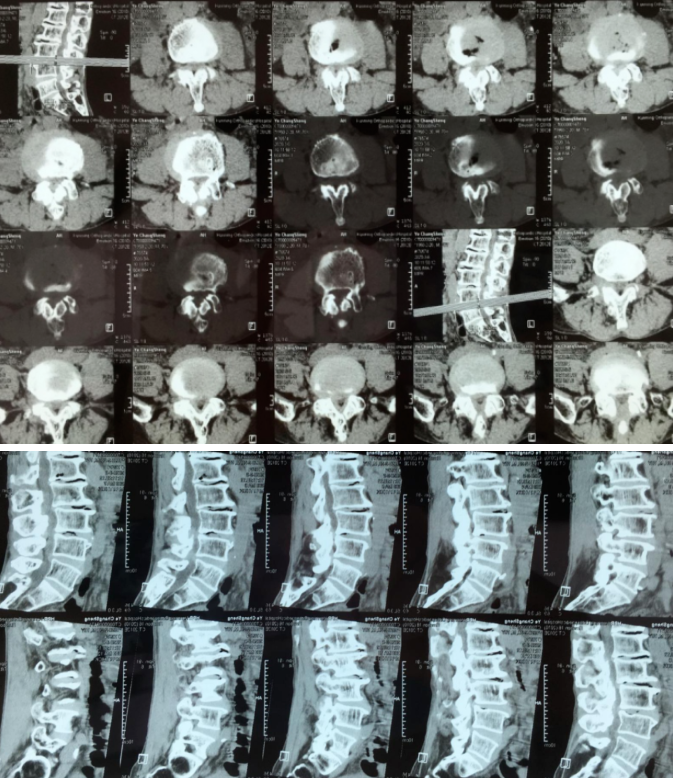

“OLIF作为一种更加微创的椎间融合术,近几年在国内各大医院逐渐开展,获得越来越多临床医生的认可”桃春辉院长介绍,该手术经左下腹腹外斜肌、腹内斜肌、腹横肌的肌间隙进入腹膜外间隙,在左侧腰大肌和腹主动脉之间安放工作通道,可通过大血管间隙及腰大肌间入路进行手术,可明显减少手术创伤、缩短手术时间、减少术中出血、缩短住院时间及患者康复时间。